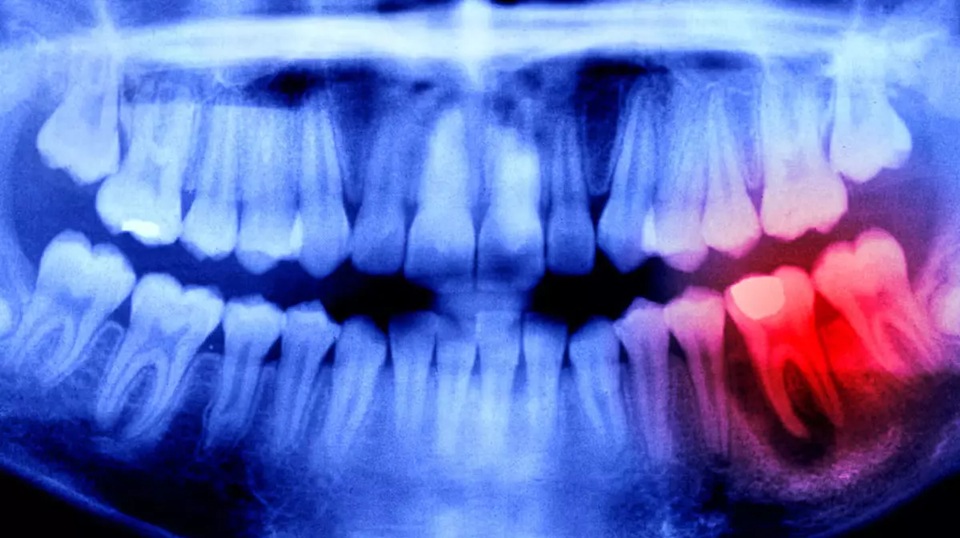

Her insanın ağız yapısında, aslında üçüncü bir diş setinin temelleri (uyuyan diş tomurcukları) halihazırda bulunuyor. Ancak vücudumuzdaki USAG-1 adlı özel bir protein, bu tomurcukların büyümesini baskılıyor. Dr. Takahashi’nin geliştirdiği ilaç, tam da bu proteini hedef alıyor. Protein engellendiğinde, "uyuyan" dişler uyanıyor ve tıpkı çocukluktaki gibi doğal bir şekilde diş etinden yükselmeye başlıyor.

Eylül 2024: En az bir dişi eksik olan 30-64 yaş arası yetişkin erkekler üzerinde insanlı deneyler başladı.

Sıradaki Adım: Yetişkinlerde sorun yaşanmaması durumunda, 2-7 yaş arası diş gelişim sorunu yaşayan çocuklar çalışmaya dahil edilecek.

Genel Kullanım: Bilim insanları, 2030 yılı itibarıyla ilacın eczanelerdeki yerini alacağına ve implant ihtiyacını ortadan kaldıracağına inanıyor.